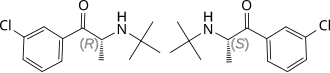

| Énantiomères S (en haut) et R (en bas) du bupropion | ||

| Nom UICPA | (RS)-1-(3-chlorophényl)-2-(tertbutylamino)propan-1-one | |

| Formule | C13H18ClNO [Isomères] |

| Masse molaire[1] | 239,741 ± 0,014 g/mol C 65,13 %, H 7,57 %, Cl 14,79 %, N 5,84 %, O 6,67 %, |

La dénomination commune internationale (DCI) « bupropione » est apparue en l'an 2000 en remplacement de sa dénomination originelle « amfébutamone », la molécule étant similaire à l'amphépramone (diéthylpropion), dans la classe des amphétamines.

Son nom chimique est β-keto-3-chloro-N-tert-butylamphetamine. C'est une cathinone substituée. Elle a donc un effet légèrement psychostimulant. Son mécanisme d'action est lié à l'inhibition de la recapture de la noradrénaline et de la dopamine. Elle se lie spécifiquement aux transporteurs de la dopamine, mais son effet comportemental a souvent été attribué à l'inhibition de la recapture de la noradrénaline. Il agit aussi comme antagoniste aux récepteurs nicotiniques de l'acétylcholine. Le bupropione appartient à la classe chimique des aminocétones et elle a une ressemblance avec les amphétamines et les phénéthylamines en général.